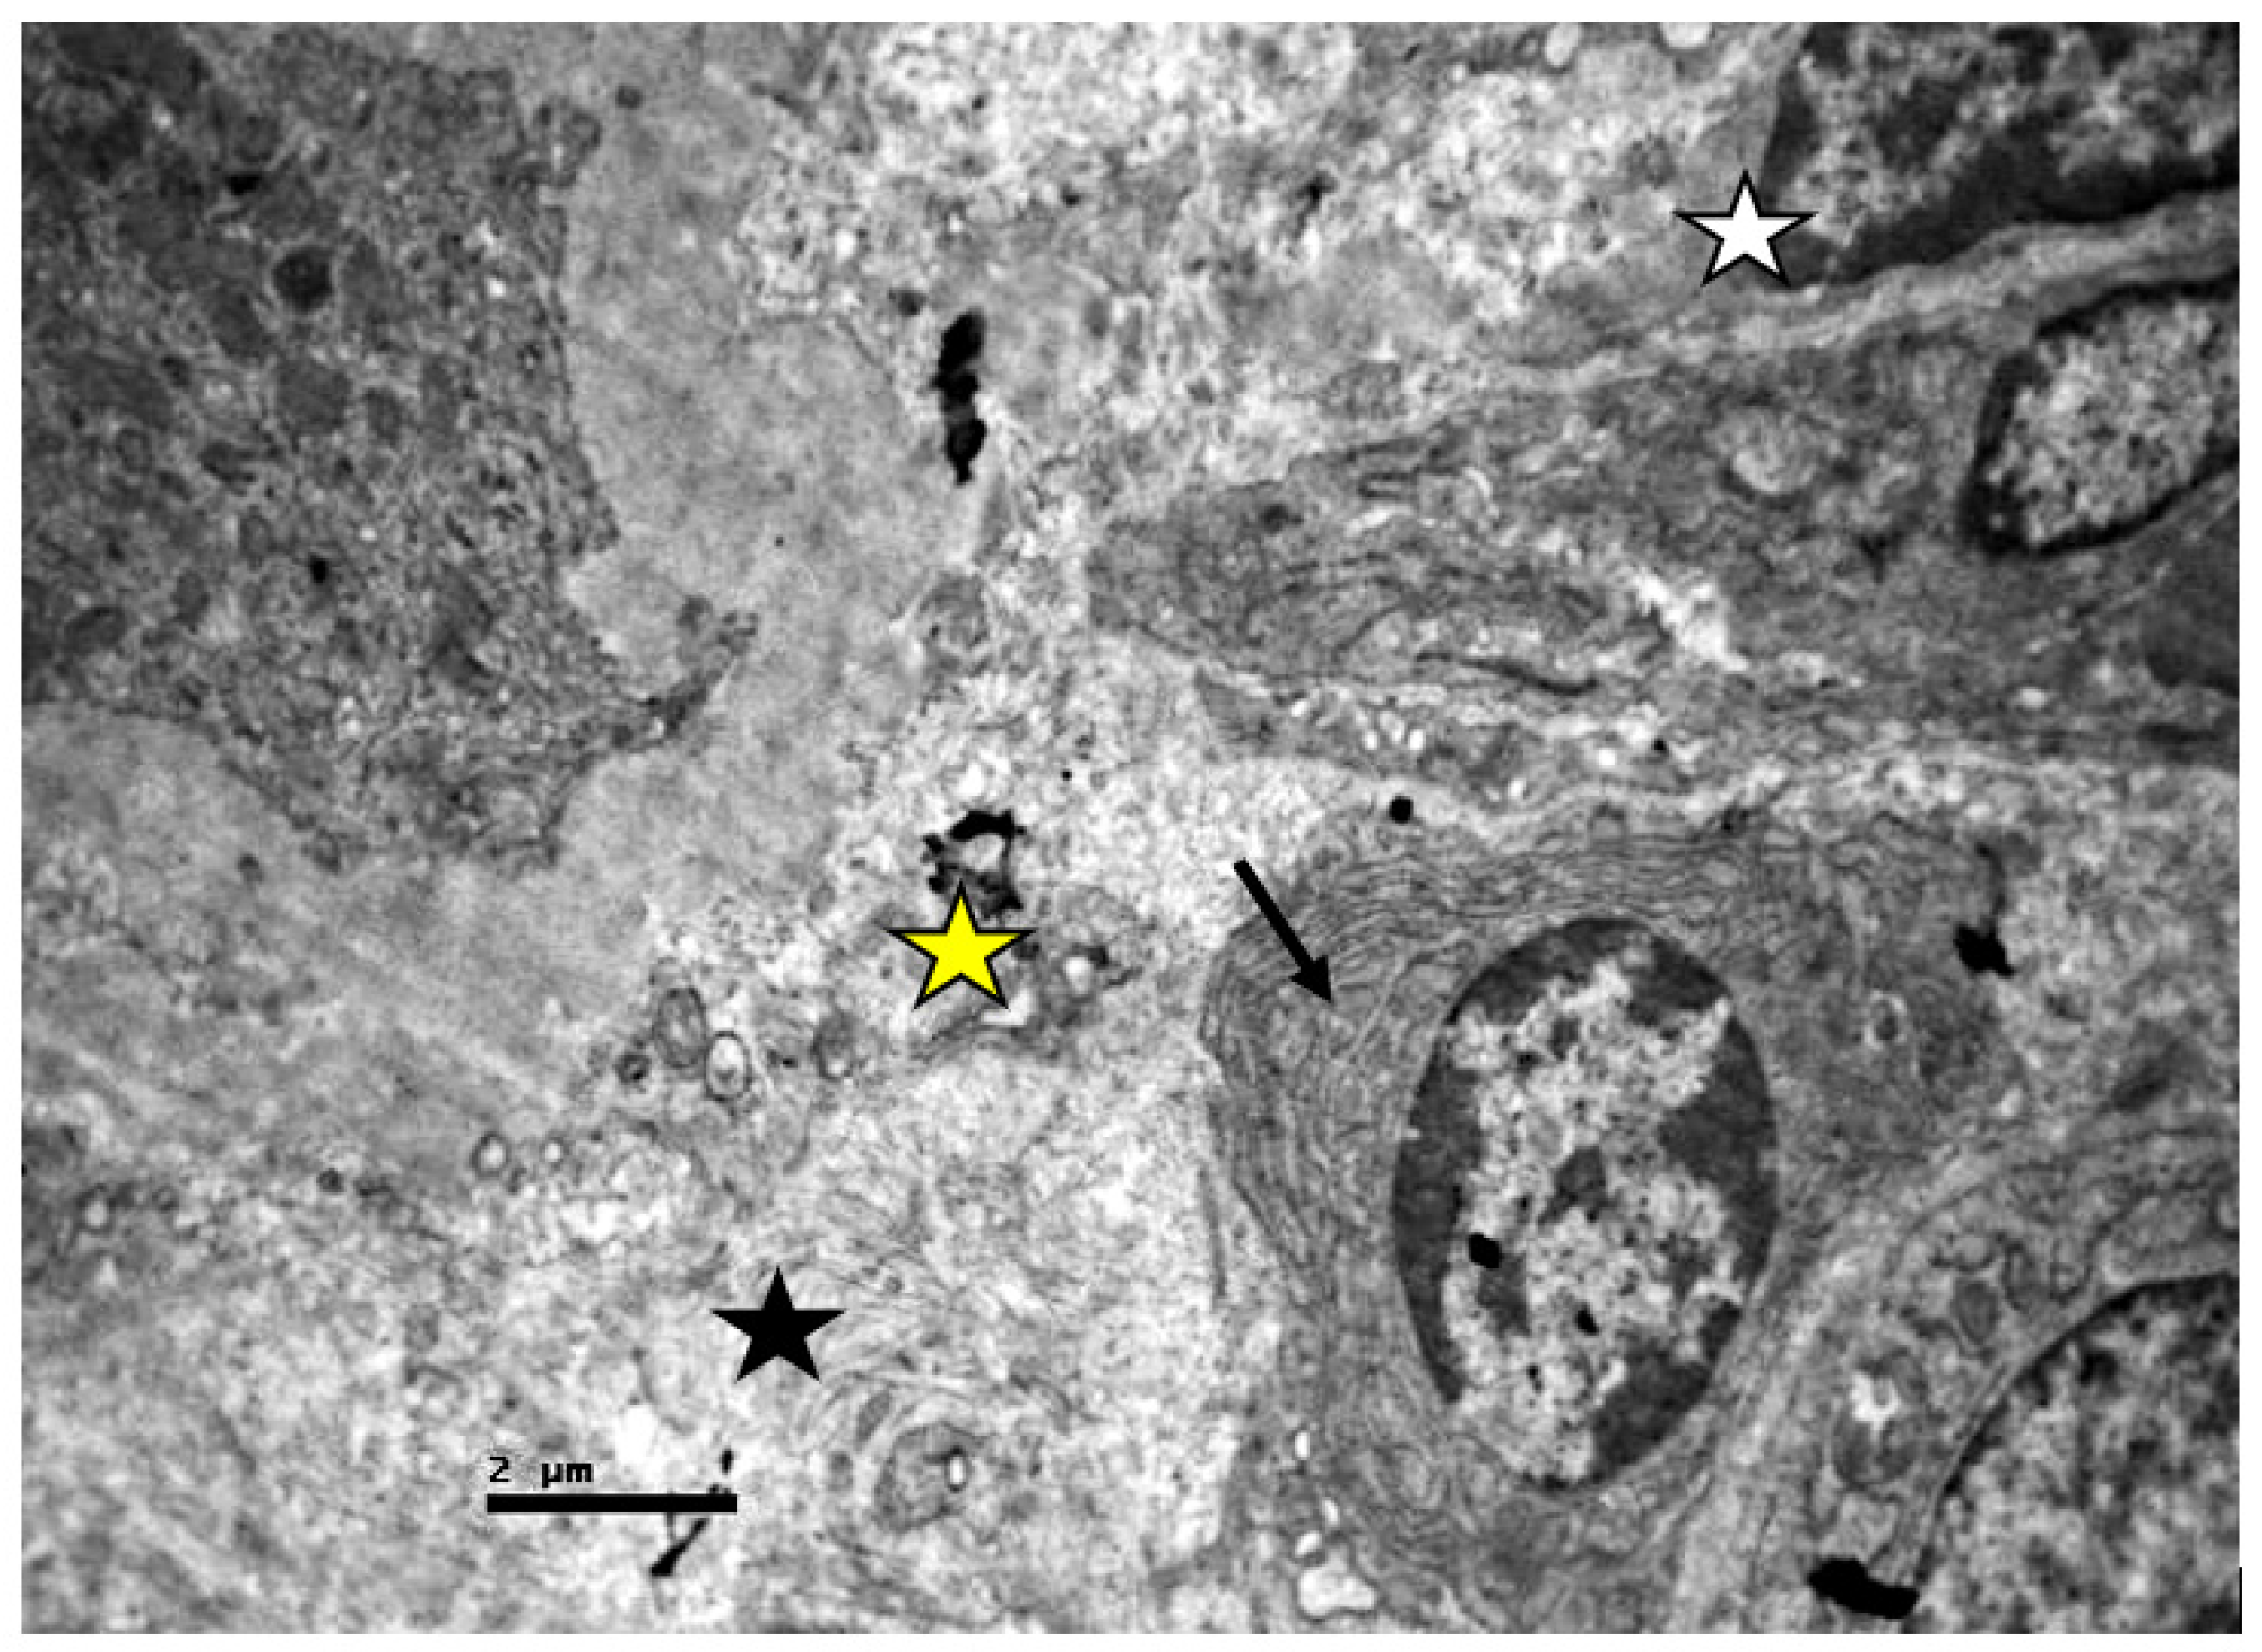

2.2. Electron Microscopic Evaluation